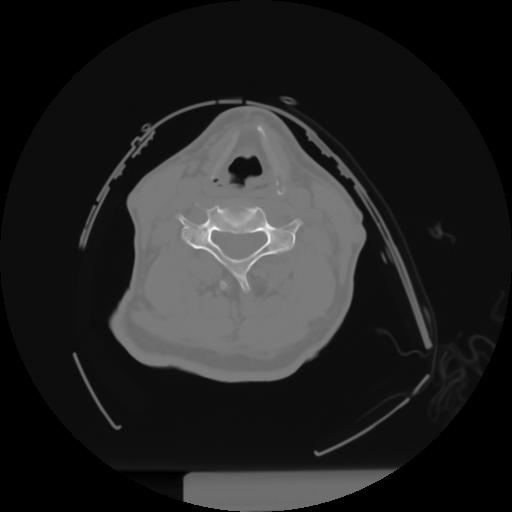

10 P.BLANDAS,,Axial,2.0,P.BLANDAS,,